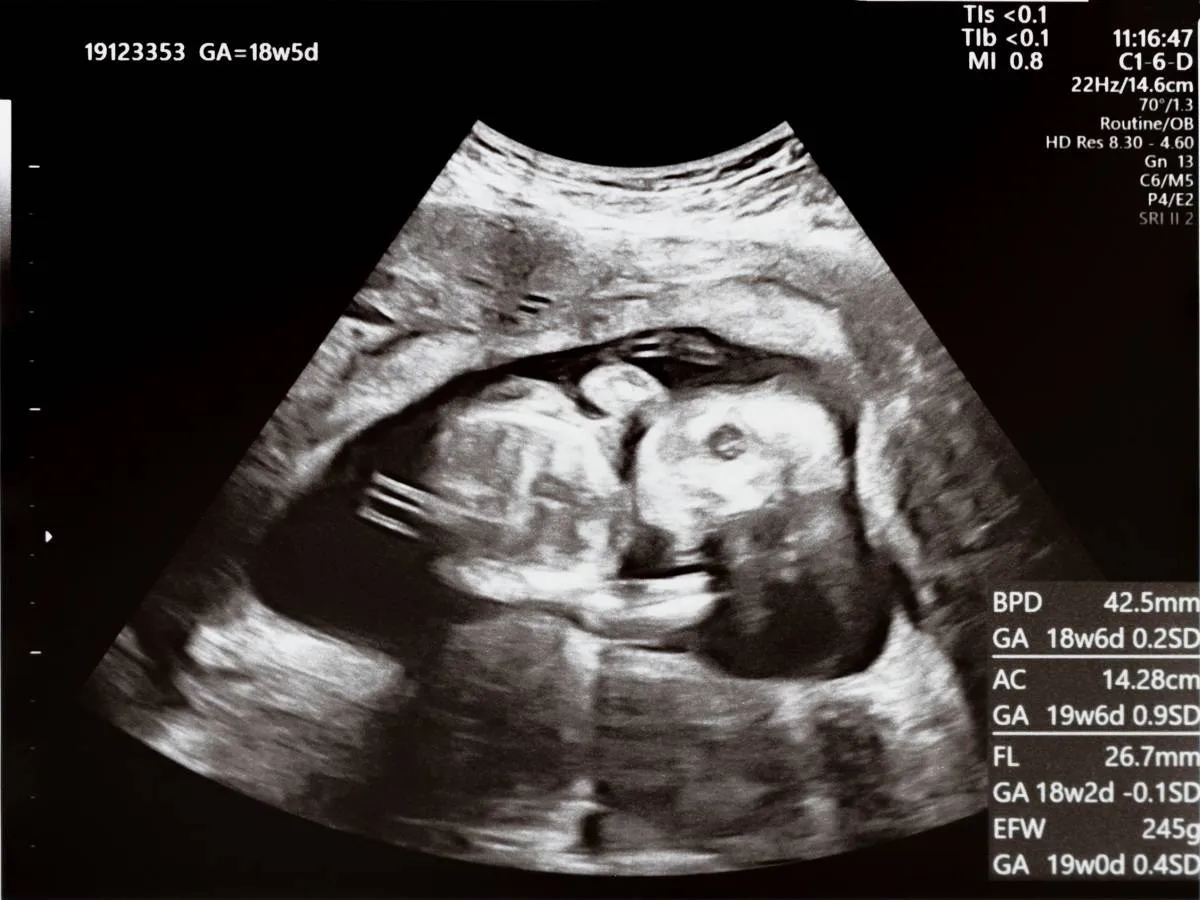

1. تصوير بالموجات فوق الصوتية

سيقوم طبيب النساء والتوليد بإجراء فحص بالموجات فوق الصوتية؛ للكشف عن حالة الجنين، والتحقق من نموه وسلامة المشيمة.